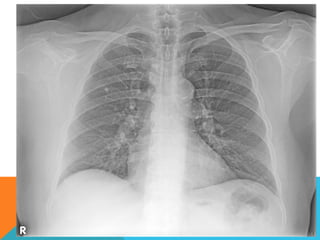

El estudio radiológico simple

evidencia una lesión nodular

menor del centímetro,

radiodensa, caracterizada como

granuloma cálcico.

En mi opinión el estudio de

TCAR fue realizado por ese

motivo y ello permito identificar

los hallazgos “floridos” que ya

se señalan y se muestran en las

imagen axiales ya

seleccionadas.

ABORDAJE TÉCNICO: Serealiza estudio con ventana mediastinal y de parénquima pulmonar con técnica de ALTA RESOLUCION, en inspiración y espiración, mediante  cortes axiales, desde ápices hasta bases pulmonares, con las siguientes observaciones En las partes blandas y las estructuras óseas dentro de los límites de la normalidad. Las regiones axilares libres. Ambos pulmones con neumatización conservada, con sobredistensión pulmonar, y áreas de atrapamiento aéreo, bilateral con cambios fibrosos cicatriciales apicales derechos. Se demuestran áreas de condensación en topografía predominantemente parenquimatosa pulmonar derecha, la mayor de ellas evidenciada hacia la base, acompañada de broncograma aéreo, la medición máxima al corte axial de 6.1 por 2.2 cm, en topografía del segmento posterior del lóbulo inferior, S10 así como también otra más se definen topografía de similares características en topografía del segmento medial del lóbulo medio, S5. En topografía parenquimatosa pulmonar izquierda imagen de similares características a las ya descritas en topografía del segmento lingular inferior, S4. No hay derrame ni áreas de engrosamiento pleurales. El patrón vascular es de características normales donde no se delimitan imágenes de lesiones aneurismáticas únicamente cambios por aortoesclerosis incipiente. El corazón de dimensiones conservada, de contornos regulares, sin desplazamientos; en la región hiliar derecha se define adenopatía de medición máxima corte axial de 1.6 por 1.4 cm.

El estudio radiológicosimple evidencia una lesión nodular menor del centímetro, radiodensa, caracterizada como granuloma cálcico. En mi opinión el estudio de TCAR fue realizado por ese motivo y ello permito identificar los hallazgos “floridos” que ya se señalan y se muestran en las imagen axiales ya seleccionadas.